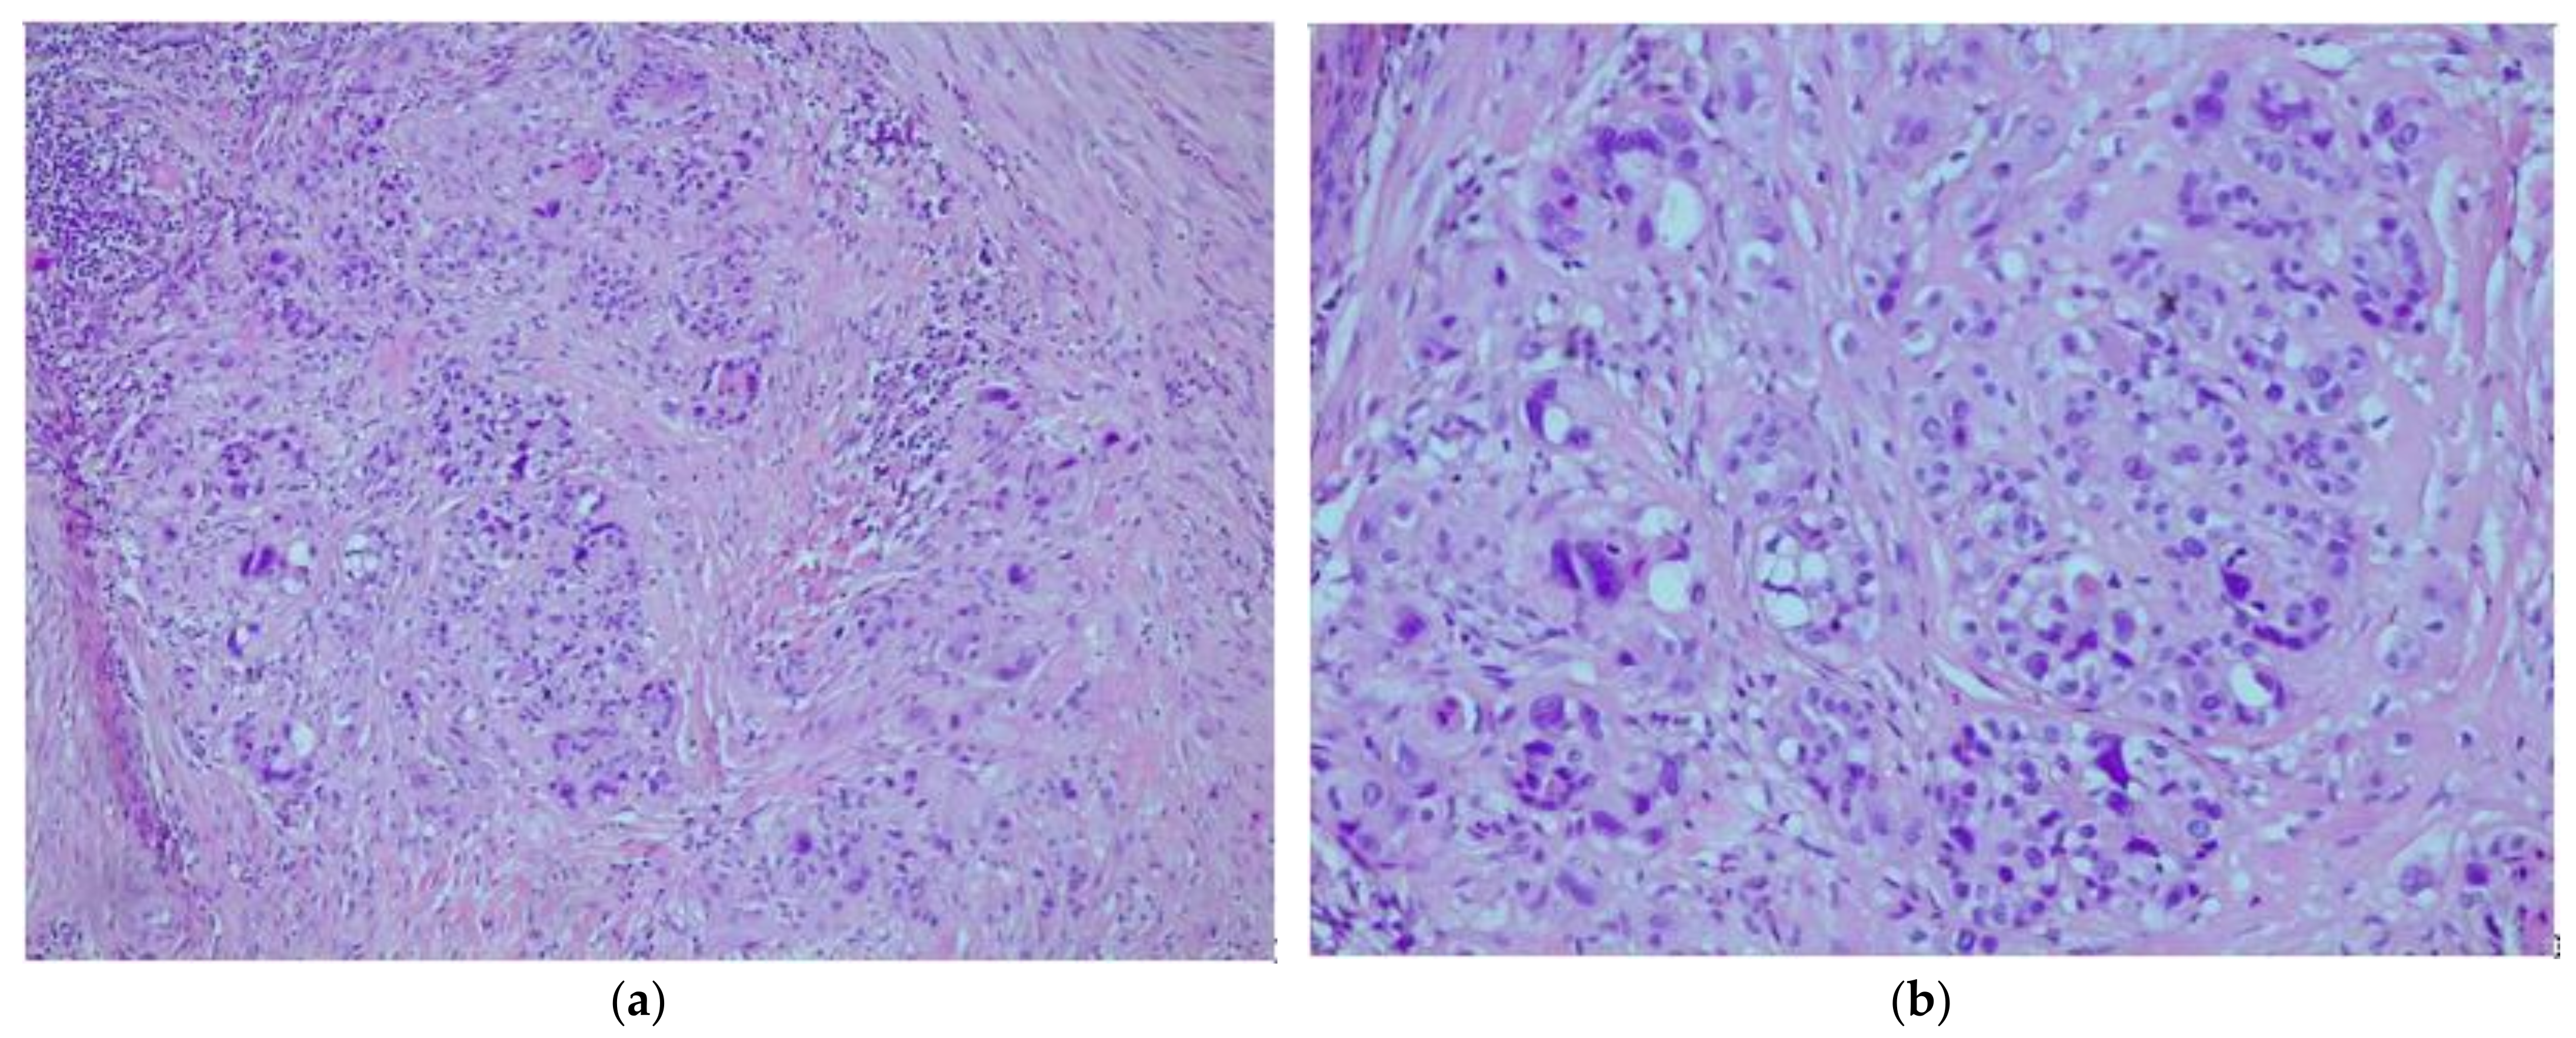

2. Case Report